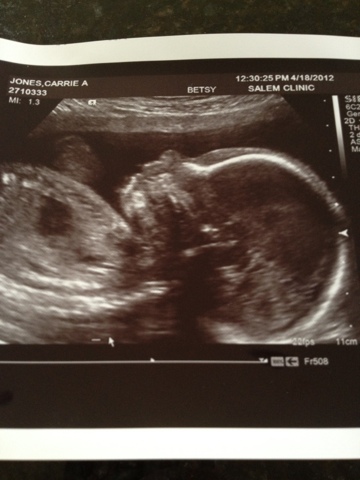

It's been a long three weeks but our prayers have been answered.

3 weeks ago, after our mid pregnancy ultrasound, we received news that our baby boy had choroid plexus cysts on his brain. The doc scheduled us to be seen with the perinatologist from OHSU to do a more detailed level 2 ultrasound.

I was terrified. Worst case scenario if they found any other markers: our baby had Trisomy 18 - a chromosomal defect where there are 3 number 18 chromosomes instead of two... Not compatible with life and would most likely die in utero or soon after birth.

A bit scary, no? Words cannot explain the fear I felt. I turned to God. I prayed. I let Him have this little boy knowing that He would take care of my little man. I can't say there weren't nights when I cried myself to sleep begging God for the health of my unborn son.

But here I am with proof in my belly that prayer works. We had our ultrasound today and the cysts are completely gone and our baby is absolutely healthy and NORMAL... Exactly what we wanted. Thank you Jesus. And thank you friends and family that prayed on our behalf.